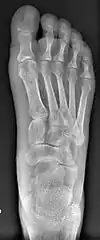

![]() Fig. 8a. Painful hallux valgus and metatarsus primus varus deformity recurrence of left foot after osteotomy surgery | |

- For recurrence correction after osteotomy procedure (Fig. 8)

Late deformity recurrence can happen after osteotomy (bone-breaking) procedures because osteotomy surgeries do not specifically stabilize first metatarsal bone.